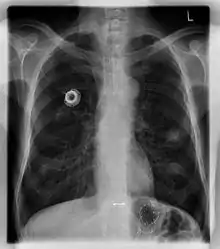

Port (medical)

In medicine, a port is a small medical appliance that is installed beneath the skin. A catheter (plastic tube) connects the port to a vein. Under the skin, the port has a septum (a silicone membrane) through which drugs can be injected and blood samples can be drawn many times, usually with less discomfort for the patient (and clinician) than a more typical "needle stick".

The port is usually inserted in the upper chest (known as a "chest port"), just below the clavicle or collar bone, with the catheter inserted into the jugular vein.

A port consists of a reservoir compartment (the portal) that has a silicone bubble for needle insertion (the septum), with an attached plastic tube (the catheter). The device is surgically inserted under the skin in the upper chest or in the arm and appears as a bump under the skin. It requires no special maintenance other than occasional flushing to keep clear. It is completely internal so swimming and bathing are not a problem. The catheter runs from the portal and is surgically inserted into a vein (usually the jugular vein or less optimally the subclavian vein). Ideally, the catheter terminates in the superior vena cava or the right atrium. This position allows infused agents to be spread throughout the body quickly and efficiently.

Ports can be put in the upper chest or arm. The exact positioning itself is variable as it can be inserted to avoid visibility when wearing low cut shirts, and to avoid excess contact due to a backpack or bra strap. The most common placement is on the upper right portion of the chest, with the catheter itself looping through the right jugular vein, and down towards the patient's heart.